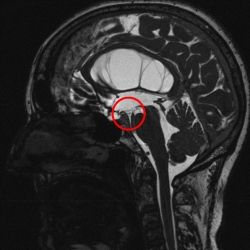

Prinzipiell stehen bei noch offener Fontanelle die Sonographie und die Kernspintomographie (MRT) zur Verfügung. Die Sonographie hat meist eine zu geringe Auflösung um zur Ursachendiagnostik eingesetzt zu werden. Die Computertomographie ist zur Ursachendiagnostik nicht sinnvoll, da der Informationsgehalt zu gering und die Strahlenbelastung für das kindliche Gehirn problematisch ist und vermieden werden soll. Somit ist die MRT die Untersuchung der Wahl. Da die diagnostische Präzision des MRT im Wesentlichen von der Qualität der Untersuchung abhängt, führen wir eine speziell auf die HIrnwasserräume abgestimmte hochauflösende Kernspintomographie, ggf. in Narkose, durch. Die Qualität dieser Aufnahmen unterscheidet sich erheblich von einer sog. „Standard-Kernspintomographie“. Mit diesem Vorgehen gelingt es häufig, zumindest eine erkennbare Ursache für einen Hydrocephalus darzustellen.

Ist die einzige Ursache des Hydrocephalus eine erworbene, umschriebene Abflussbehinderung des Hirnwassers im Bereich des sog. Aquädukt, der 4. Hirnkammer oder der Ausflussöffnung aus der 4. Hirnkammer, so kann diese Abflussbehinderung durch eine „innere Umleitung“ durch Eröffnung des Bodens des 3. Ventrikels umgangen werden.

Das hierfür verwendete Verfahren ist die endoskopische Ventrikulozisternostomie (englisch endoscopic third ventriculostomy = ETV). Hierbei wird ein feines Endoskop in die erweiterten Hirnkammern vorgeschoben und damit am Boden des 3. Ventrikels in einem Areal, welches keine Funktion enthält, unter Sicht meist mit einem Speziallaser eine Öffnung geschaffen.